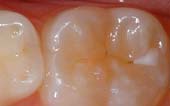

Protective Resin Restoration

A PRR is a protective coating that is applied to the chewing surfaces (grooves) of the back teeth (premolars and molars), where four out of five cavities in children are found. This resin acts as a barrier to food, plaque and acid, thus protecting the decay-prone areas of the teeth.